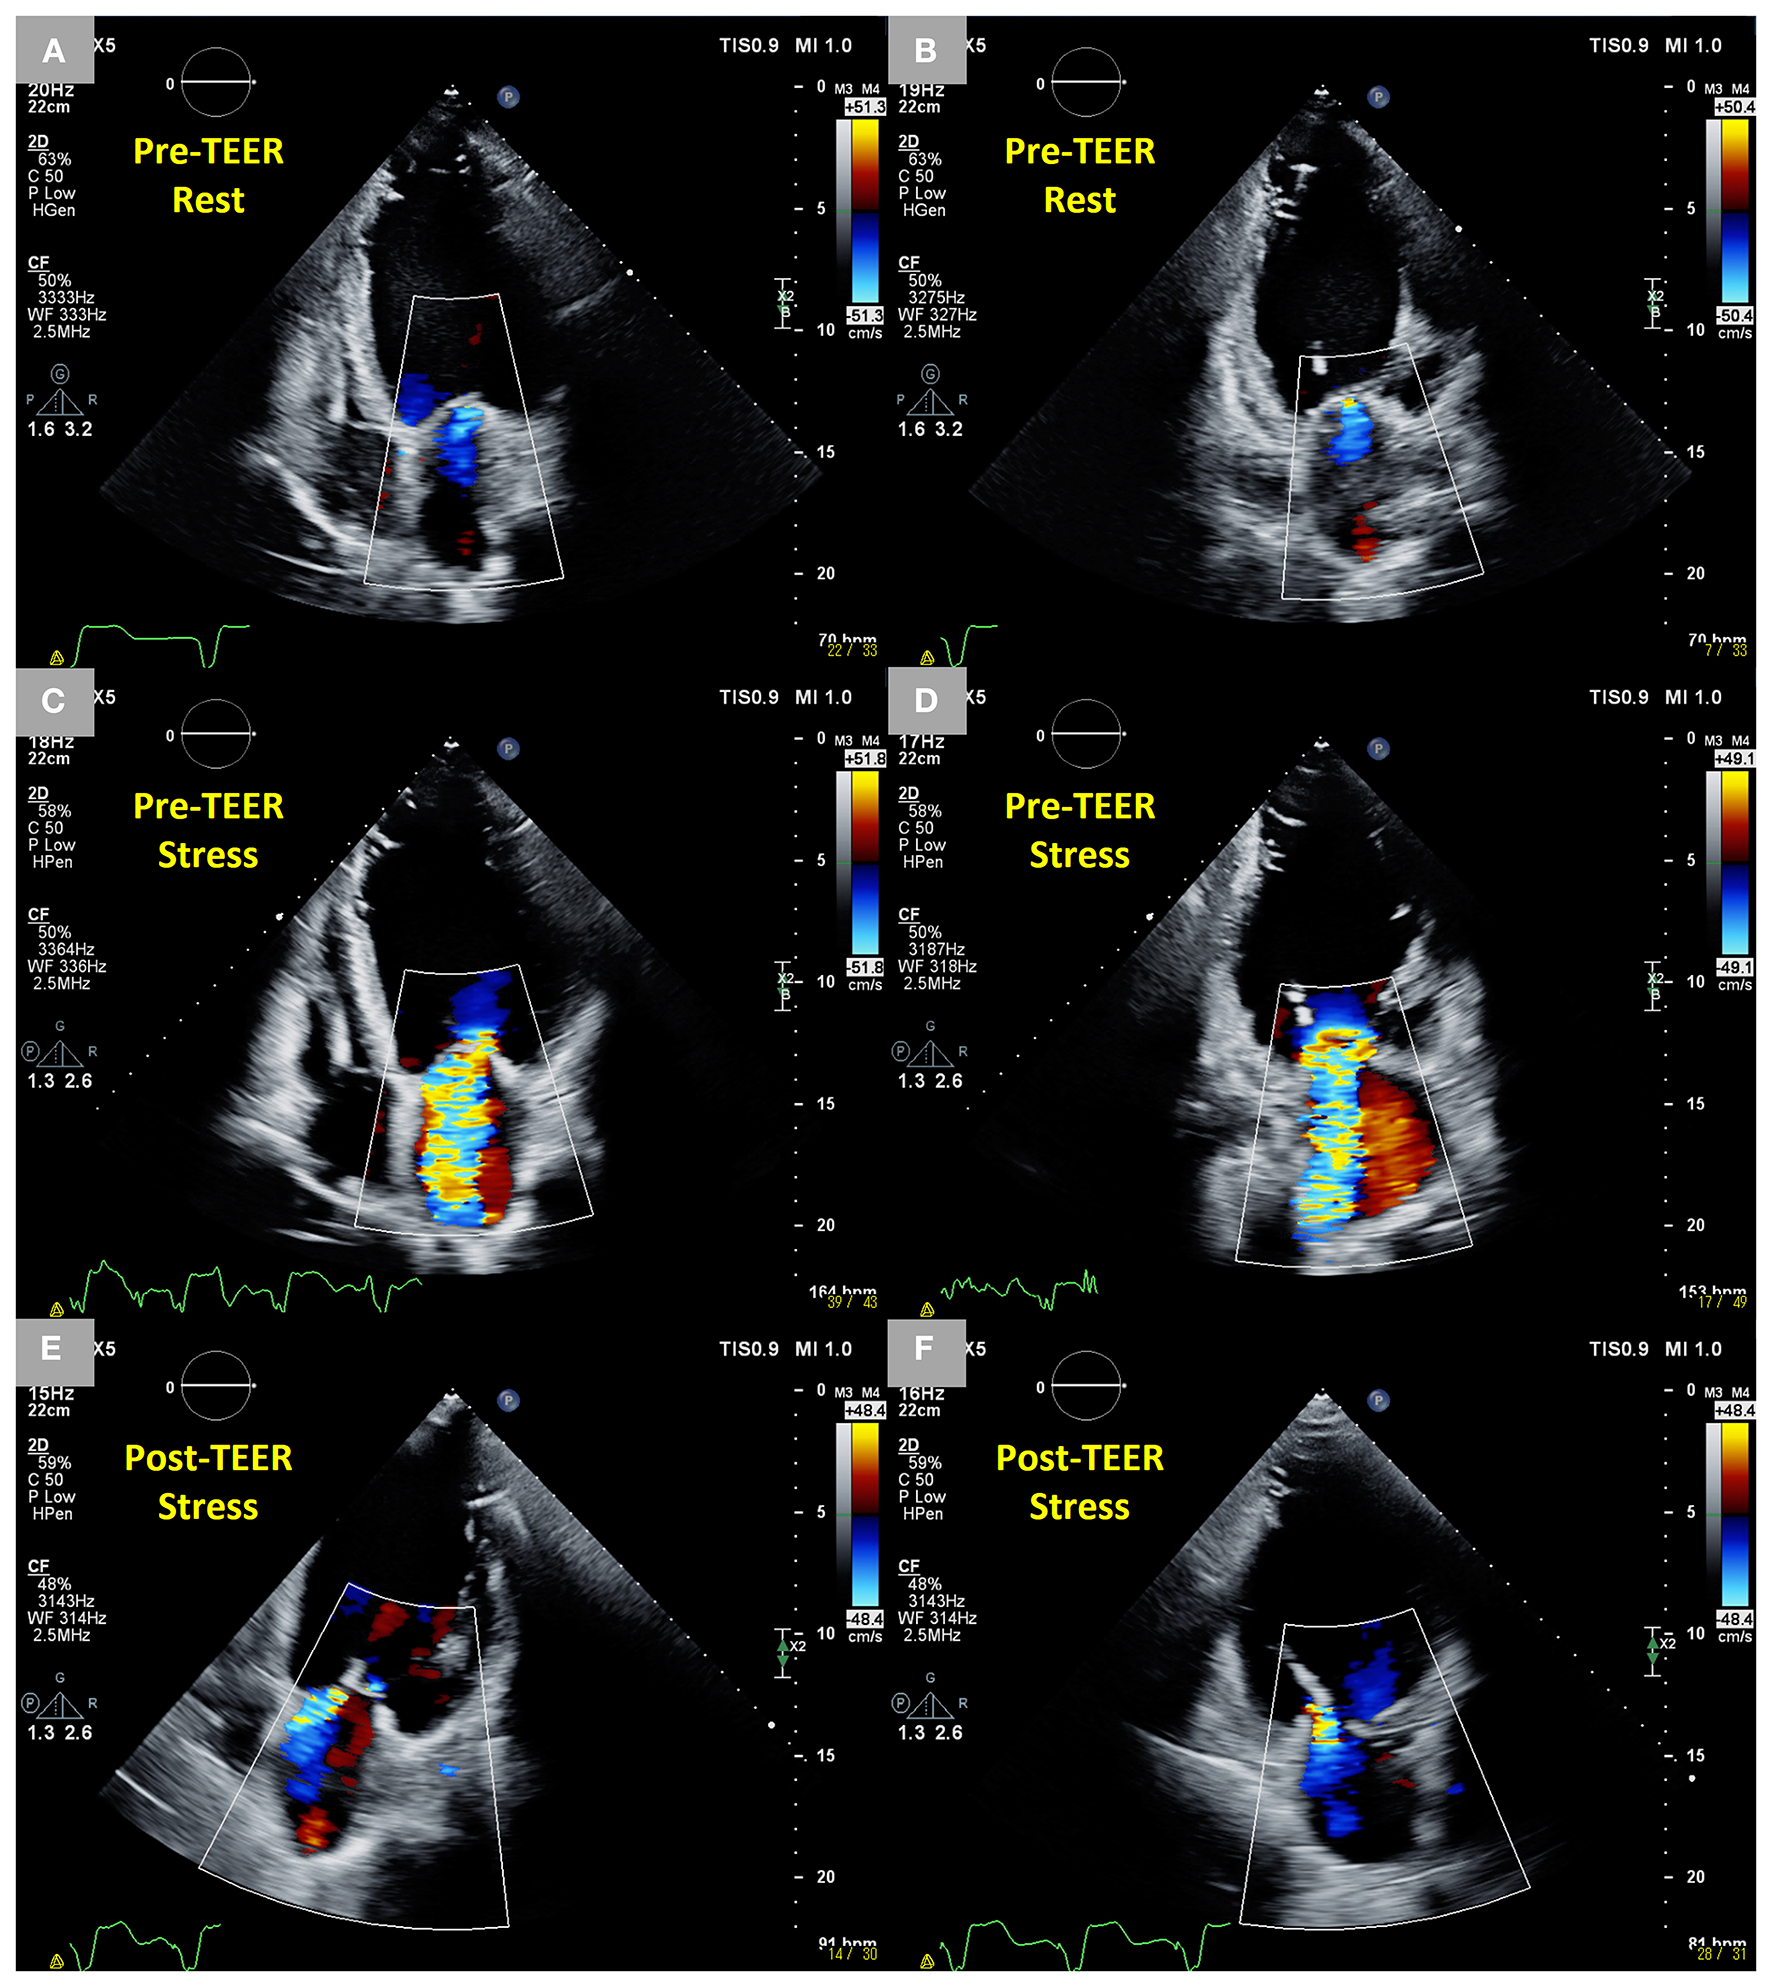

Figure 4

Dynamic changes in SMR during exercise stress echocardiography before TEER and controlled SMR following TEER during exercise stress echocardiography in an 83-year-old male patient who had an anterior and inferior old myocardial infarction and heart failure with reduced ejection fraction after CRT. (A,B) Trivial SMR at rest in two-dimensional color Doppler images from four-chamber and two-chamber views. (C,D) Dynamic severe SMR (EROA 0.52 cm2) under stress in two-dimensional color Doppler images from four-chamber and two-chamber views. (E,F) Mild MR under stress 6 months after the TEER in two-dimensional color Doppler images from four-chamber and two-chamber views. SMR, secondary mitral regurgitation; TEER, transcatheter edge-to-edge repair; CRT, cardiac resynchronization therapy; EROA, effective regurgitant orifice area; MR, mitral regurgitation.